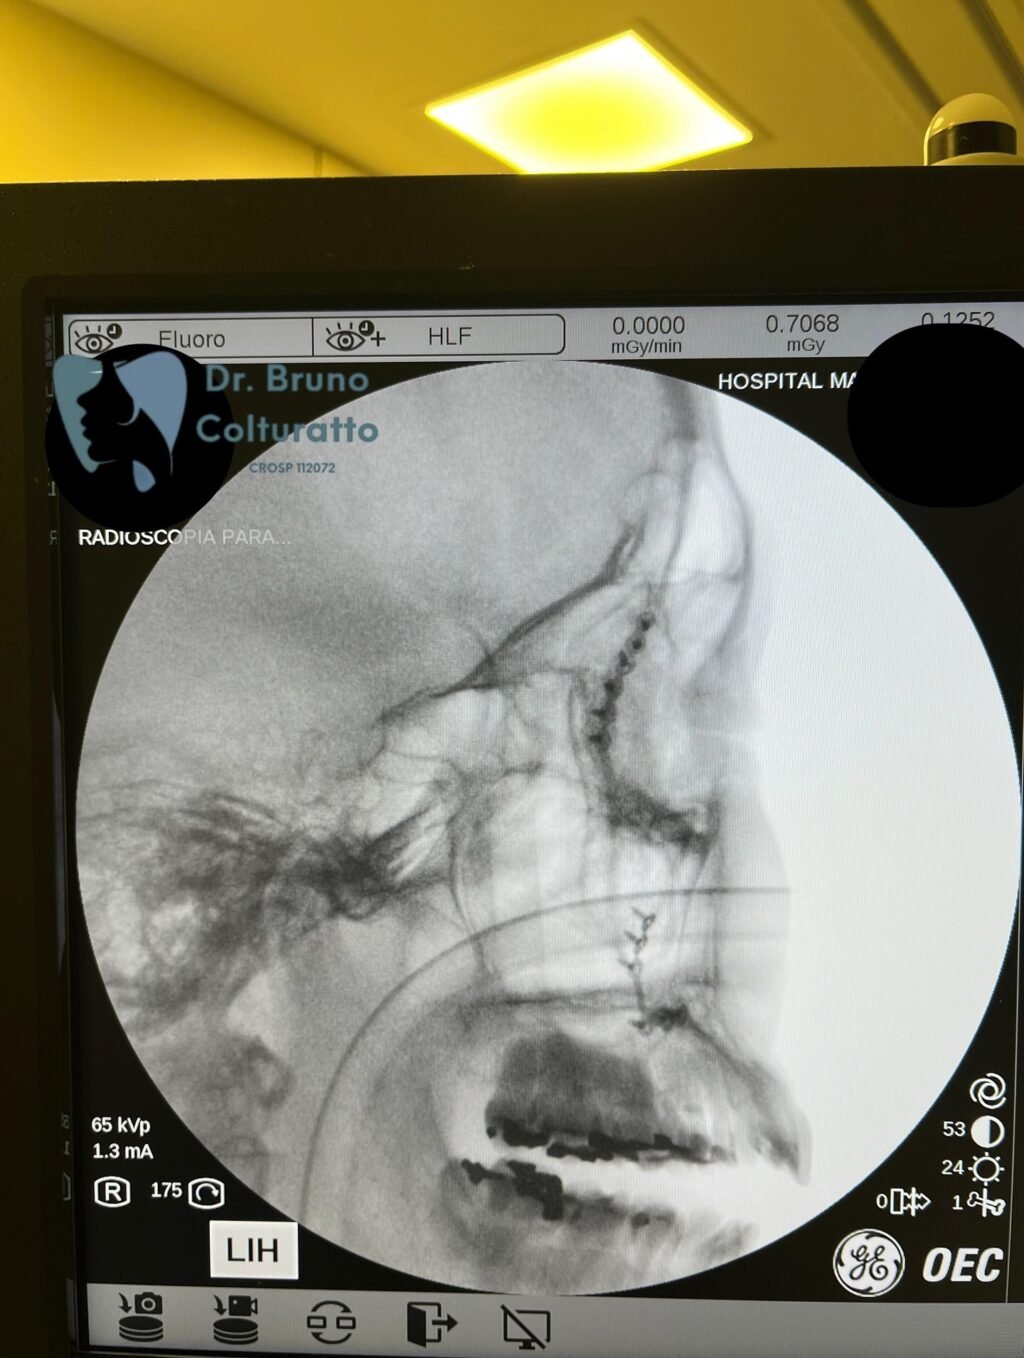

A Patologia Oral e Maxilofacial é a especialidade responsável pelo diagnóstico e tratamento de doenças que afetam a boca, mandíbula e estruturas faciais. Atua na identificação de lesões, cistos e tumores, garantindo diagnóstico preciso e tratamento adequado para preservar a saúde bucal e geral do paciente.